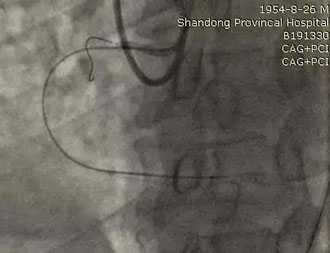

图三:将Stingray球囊送至着陆区